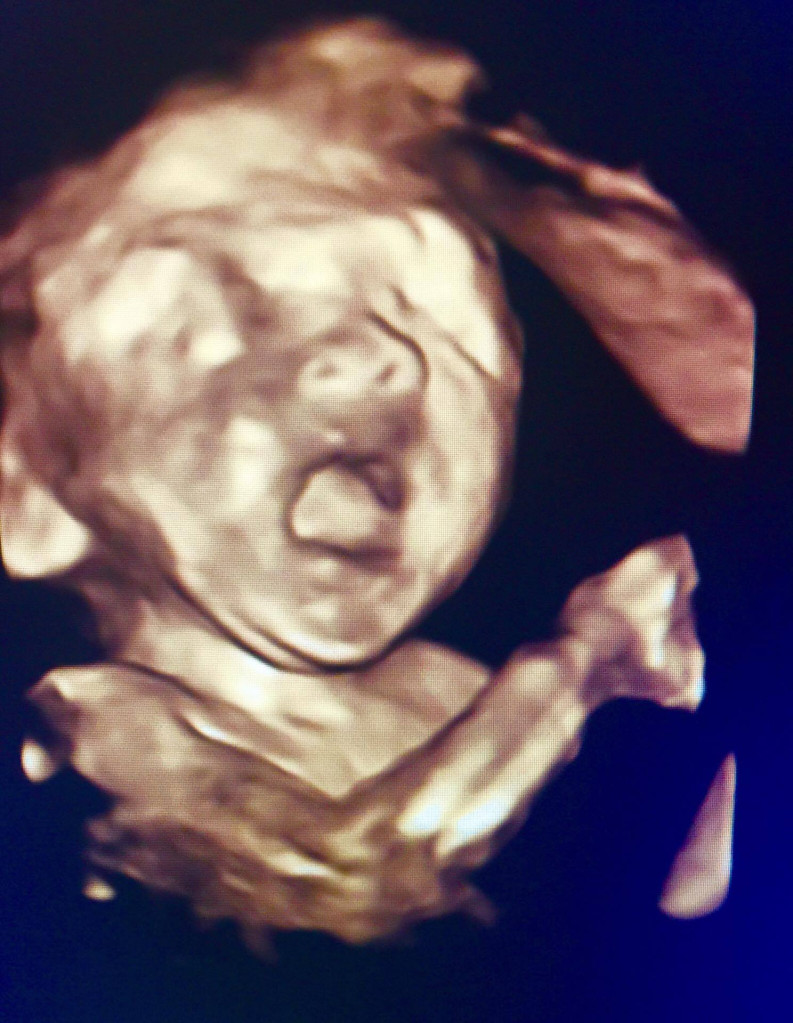

20-36週:能感覺到到各種型態的胎動,包括弱、強、滾動,隨著4D超音波的進展,寶寶在媽媽子宮內的一舉一動讓我們更加一覧無疑,他會吸吮呑咽,甚至會做鬼臉、打哈欠、會皺眉、會笑、會拳打腳踢,很多媽媽會好奇這些動作的意義為何?是不是他高興、不高興?最常見的說法我們可以把他視為關節神經肌肉的鍛練,所謂用進廢退,這樣寶寶出生後才能把肌肉運用自如。

寶寶吃手指(上圖)、寶寶揉眼睛(下圖)。動作表情已很豐富。圖/作者提供